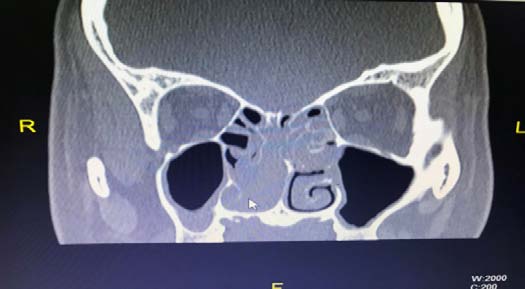

CT Scan of the nose and paranasal sinuses (PNS) revealed an enhancing mass arising from the right ethmoidal labyrinth and pushing the septum to the opposite side with expansion of the medial wall of maxilla. The mass was seen extending into posterior chonae and indenting the medial orbital wall with no bony disruption, there was no extension of the tumor into the anterior cranial fossa (Fig 1). Due to the accessibility of the mass anteriorly a punch biopsy was taken which caused profuse bleeding that was controlled with anterior nasal packing. The pack was removed after 24 hours.